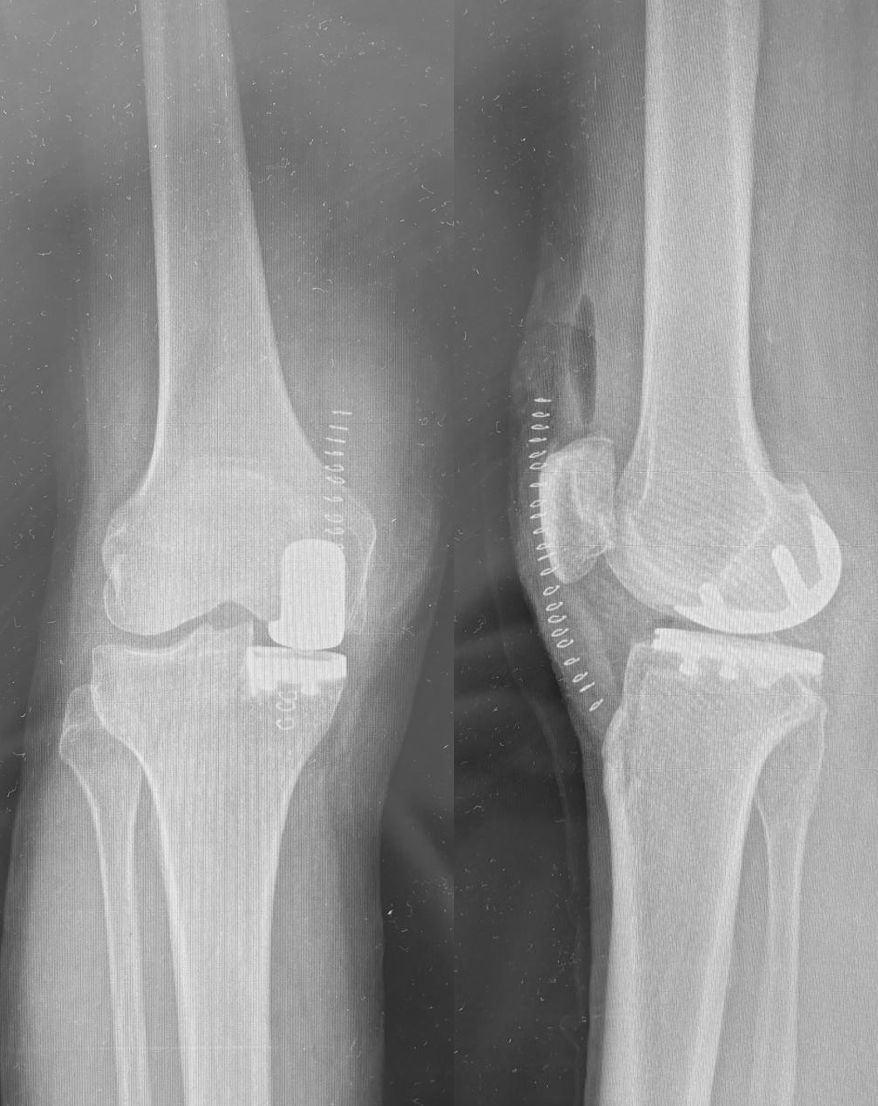

Ho maturato una solida esperienza nella chirurgia protesica mini-invasiva di anca e ginocchio. Eseguo interventi di protesi di anca mediante accesso anteriore “bikini” e accesso posterolaterale, interventi di protesi di ginocchio sia monocompartimentale che totale. Tratto la traumatologia sportiva di ginocchio e spalla mediante l’utilizzo di tecniche artroscopiche mini-invasive.